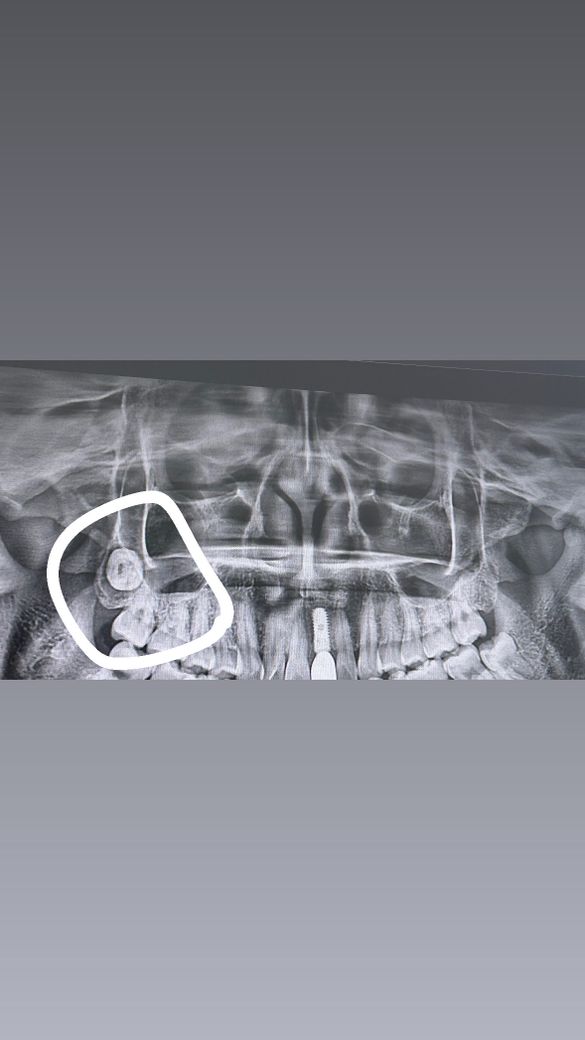

오늘 매복 사랑니 발치하고 왔는데 오른쪽 위 사랑니에 물혹이 있데요

안녕하세여 오늘 왼쪽 밑에 매복 사랑니 발치하고 왔어요 한두달전에 오른쪽 사랑니를 뽑았을땐 그 치과에선 윗 사랑니 안뽑아도 된다했는데 좀 더 전문적인데 갔더니 제 오른쪽 위에 사랑니가 하나 있는데 물혹이 둘러싸고 있고 오른쪽 위 어금니쪽이랑 가까워서 뽑아야 한다고 하드라구요 바르게 난 사랑니도 아니라 어려운수술이라 했습니다.. 좀 걱정되서요 양성낭종같은데 많이 심각한건가요

사진으로 봤을 경우에는 매복 사랑니가 매우 깊은 곳에 있는 것으로 보입니다. 일반 병원에서는 발치가 힘들 수 있습니다. 대학병원의 구강 외과에서는 깊게 위치되어 있는 사랑니도 발시할 수 있습니다.

함치성낭(dentigerous cyst) 말씀 들으신 것 같습니다 악성은 아니고 발치해주면 됩니다

아직은 낭이 심하게 커지진 않았지만 계속 커지면 잇몸뼈가 녹을 수 있습니다

발치 어렵긴 하겠네요 발치 과정에서도 뼈를 많이 쳐야할 겁니다